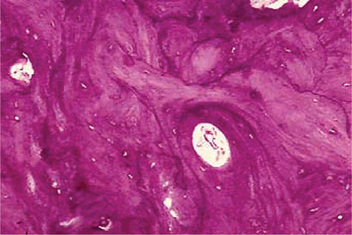

The microscopic appearance of the bone in cases of osteitis deformans varies remarkably, depending upon the stage of the disease encountered. The initial osteolytic phase is marked by disordered areas of resorption by an increased number of overtly large osteoclasts. These abnormal osteoclasts may contain as many as 100 nuclei. The subsequent osteoblastic phase follows with haphazard laying of new bone matrix and formation of woven bone without regard to the patterns of stress. Repeated episodes of bone removal and formation results in the appearance of many small irregularly shaped bone fragments that appear to be joined in a jigsaw or mosaic pattern with deeply staining hematoxyphilic reversal lines (Fig. 17-32). This pattern is the histologic hallmark of Paget’s disease. As the disease progresses, the osteoblastic phase predominates, and excessive abnormal bone formation occurs, causing more compact and dense bone. The pagetic bone is coarse and fibrous, with an avidity for calcium and phosphorus. Marrow spaces are filled with loose highly vascularized connective tissue. The hypervascular bone combined with cutaneous vasodilation causes an increase in the regional blood flow and accounts for the rise in skin temperature seen clinically. The hypervascularity consists of an increased number of patent capillaries and dilated arterioles, as well as of larger venous sinuses (Fig. 17-33).

Figure 17-32 Osteitis deformans.

Photomicrographs of bone in different stages showing (A) reactive phase, (B) mosaic pattern, and (C) resting phase. Note the prominent resting and reversal lines in B.

Figure 17-33 This photomicrograph taken from a bone biopsy from a patient with Paget’s disease of bone shows several bone spicules in a highly vascularized connective tissue stroma.

These areas of bone formation alternate with areas of bone resorption characterized by the presence of osteoclasts. Typically, the osteoclasts are seen inside of Howship lacunae.

The normal trabecular appearance is distorted with a mosaic pattern of irregular cement lines joining areas of lamellar bone. Pagetic bone shows no tendency to form Haversian systems or to center on blood vessels; the bones are very hard and dense. Eventually, the osteoblastic activity diminishes, and an osteoporotic or burned-out phase predominates (Figs. 17-34, 17-35). The new bone is disordered, poorly mineralized, and lacks structural integrity. The proliferation of bone and concomitant hypercementosis sometimes result in obliteration of the periodontal ligament.